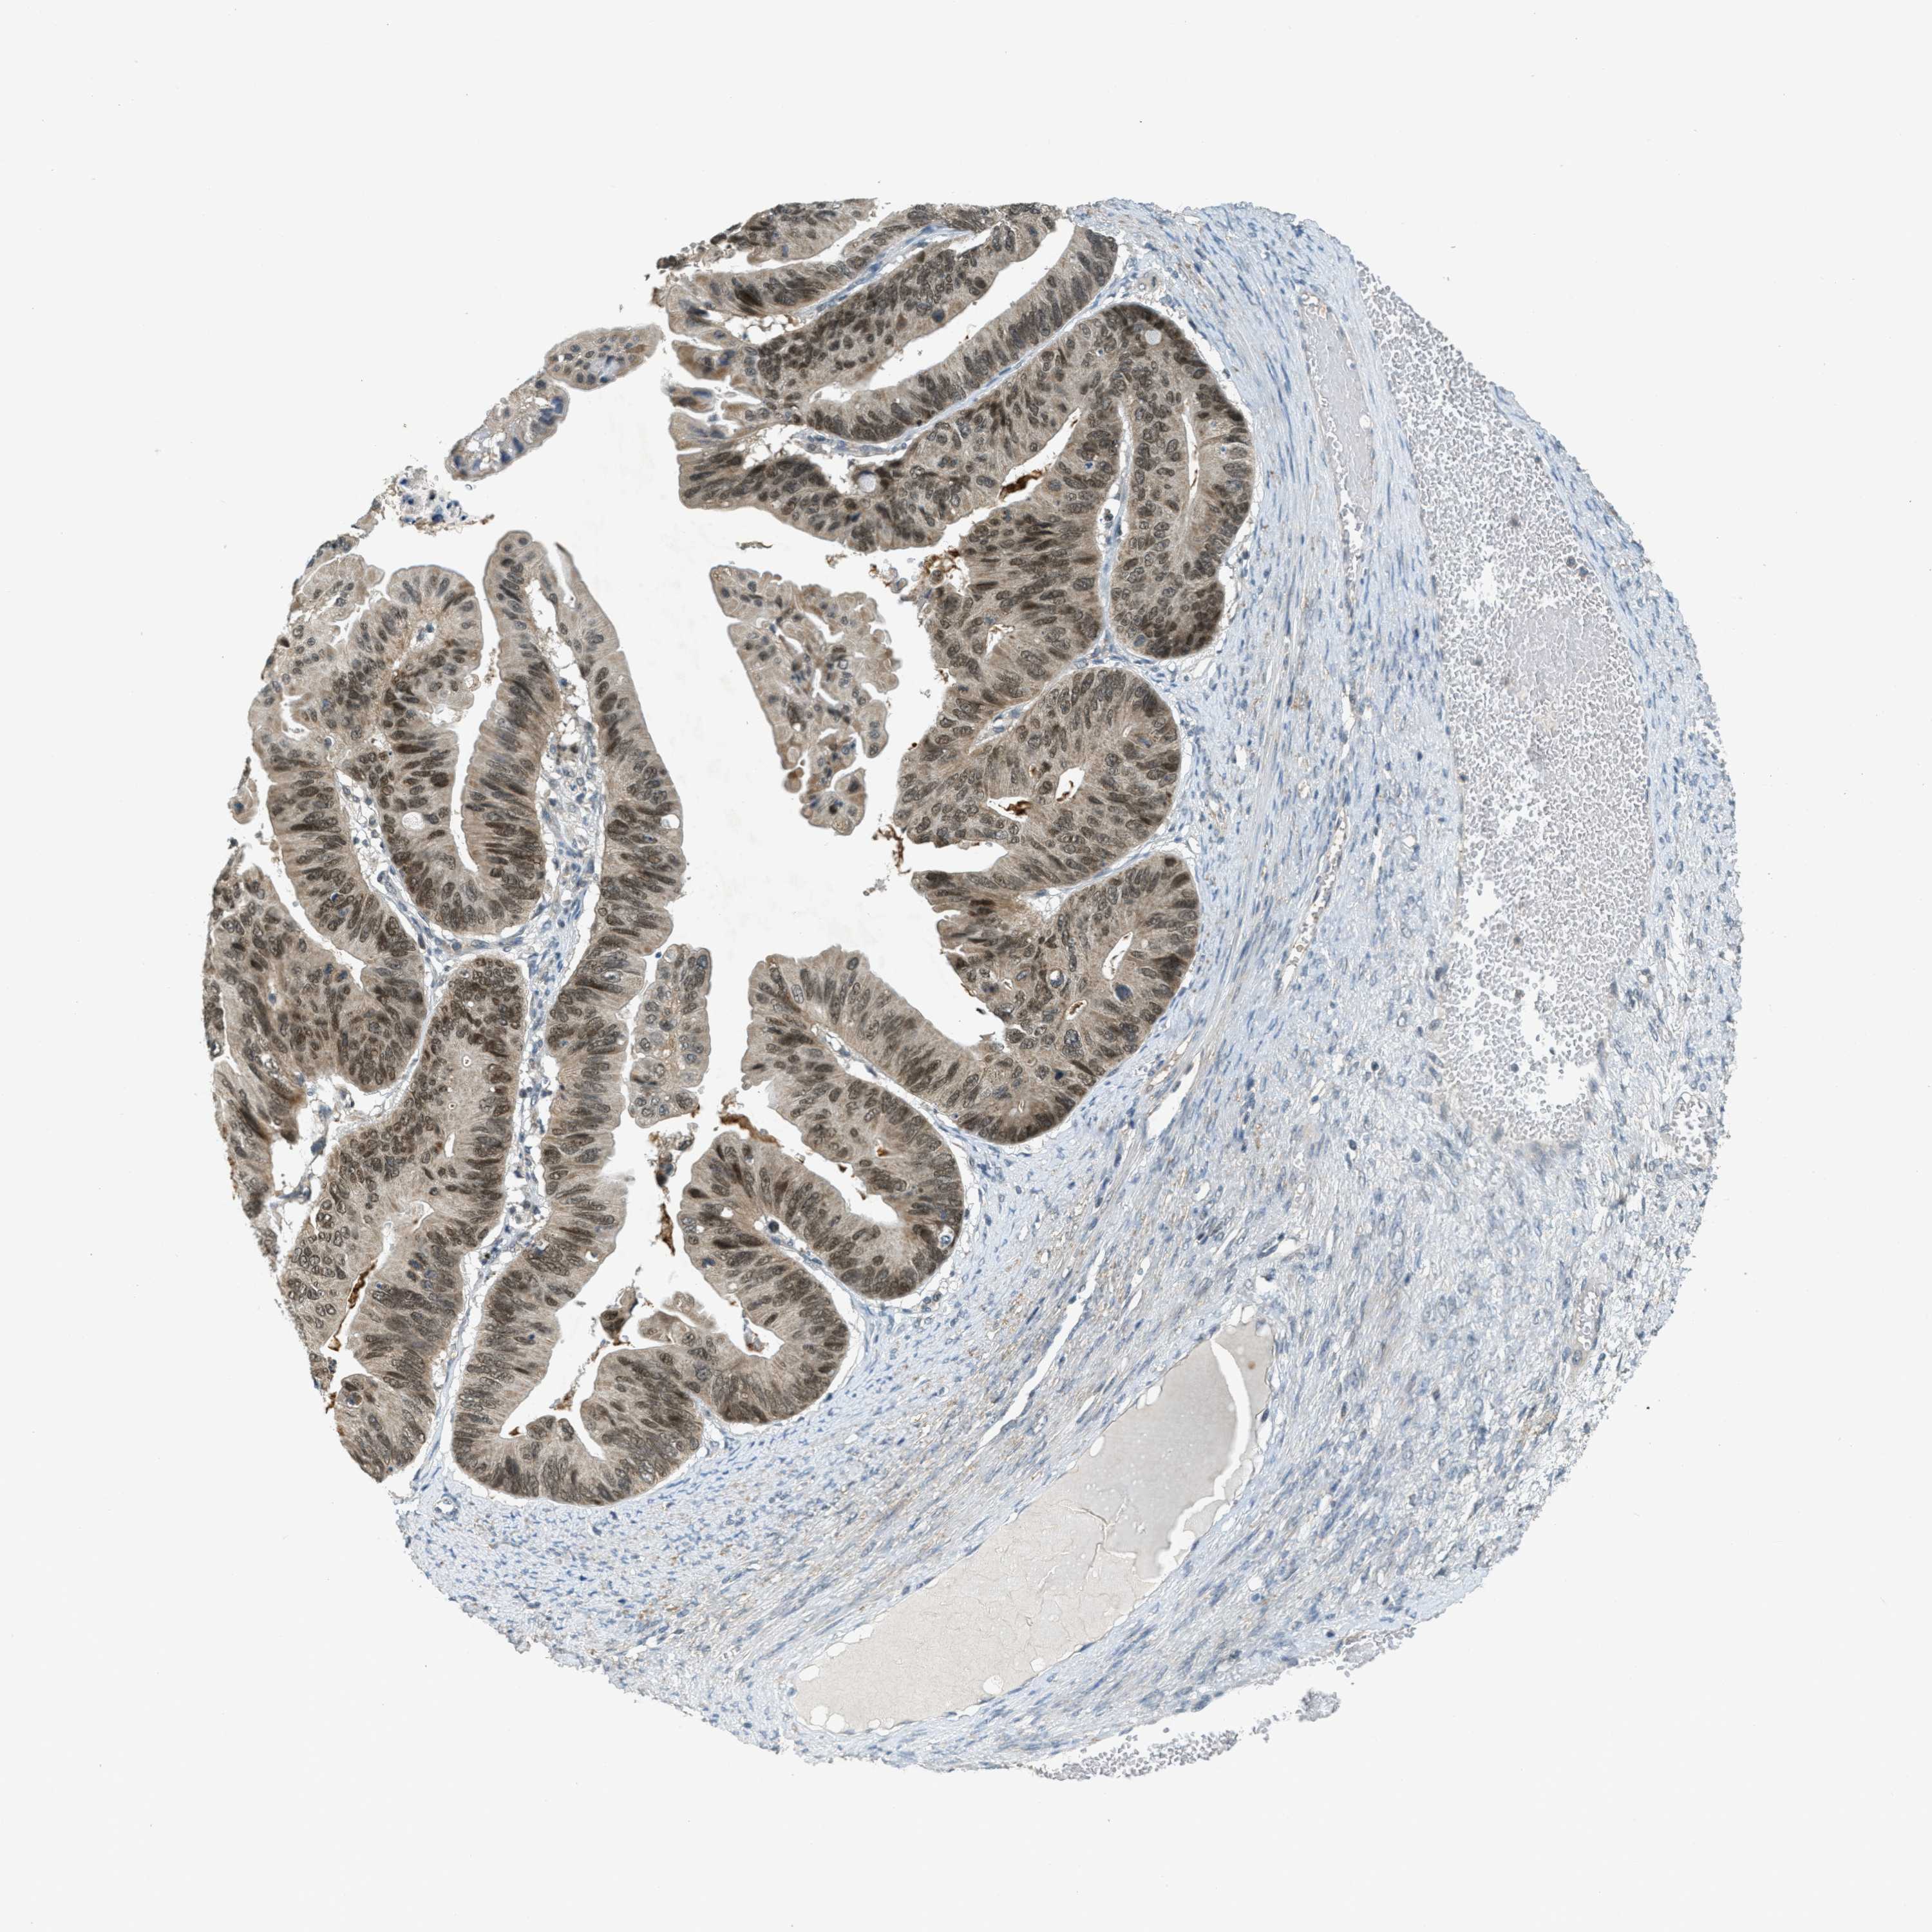

OVARIAN CANCER - Protein expressioni

A mouse-over function shows sample information and annotation data. Click on an image to view it in a full screen mode. Samples can be filtered based on level of antibody staining by selecting one or several of the following categories: high, medium, low and not detected. The assay and annotation is described here.

Note that samples used for immunohistochemistry by the Human Protein Atlas do not correspond to samples in the TCGA dataset.

Antibody stainingi

Antibody staining in the annotated cell types in the current human tissue is reported as not detected, low, medium, or high, based on conventional immunohistochemistry profiling in selected tissues. This score is based on the combination of the staining intensity and fraction of stained cells.

Each image is clickable and will lead to virtual microscopy that enables deeper exploration of all samples and also displays staining intensity scores, fraction scores and subcellular localization as well as patient and tissue information for each sample.

Antibody HPA036786

Antibody CAB017849

Staining

High

Medium

Low

Not detected

Intensity

Strong

Moderate

Weak

Negative

Quantity

>75%

75%-25%

<25%

None

Location

Nuclear

Cytoplasmic/membranous

Cytoplasmic/membranous,nuclear

Cystadenocarcinoma, serous, NOS

Carcinoma, endometroid

Cystadenocarcinoma, mucinous, NOS

Carcinoma, NOS